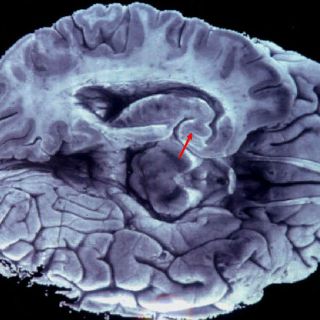

Puebla (12/JUN/2013).- Investigadores del Instituto Nacional de Astrofísica, Óptica y Electrónica (INAOE) presentarán esta semana a inversionistas de Estados Unidos, el sistema que crearon para rehabilitar a pacientes con embolia cerebral.

Este mecanismo está diseñado para rehabilitar las extremidades superiores de los pacientes, para ello, se diseñó una manija especial, para detectar el movimiento del brazo de la persona a rehabilitar y también detectar la presión de la mano.

A través de este elemento, se interactúa con un sistema de realidad virtual, consistente en juegos diseñados, especialmente para la rehabilitación.